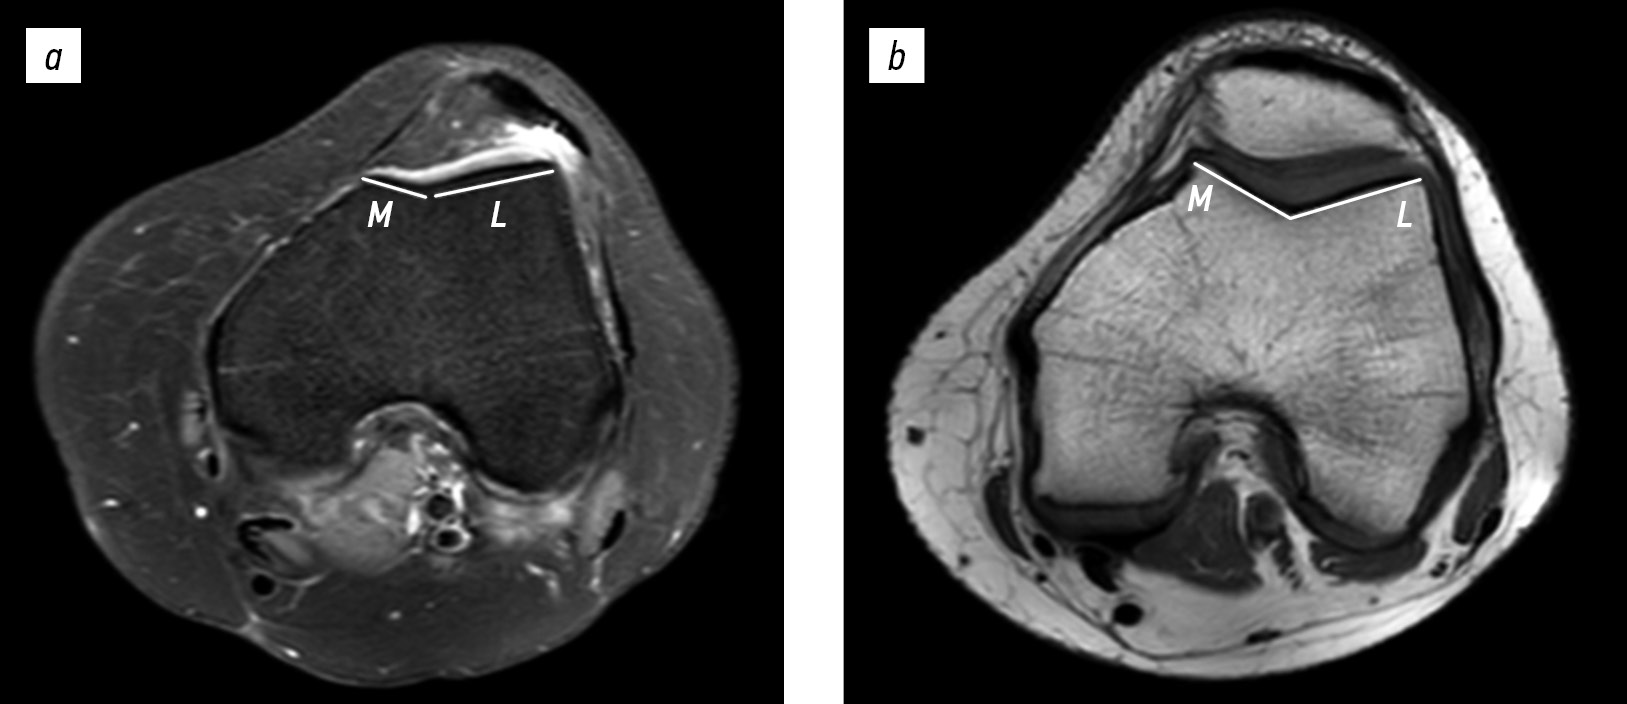

Trochlear facet asymmetry was evaluated on axial MRI images without fat suppression, using the first slice on which the articular cartilage was visible. Trochlear groove asymmetry was measured as the ratio of the medial facet to the lateral facet. The length of the medial facet (M) and of the lateral facet (L) were measured to obtain facet asymmetry; the length of the medial facet was divided by the length of the lateral facet and expressed as percentage (M/L × 100%). A ratio of the trochlear facets below 40% was indicative of trochlear dysplasia (Fig. 2) [13].

Fig. 2. Trochlear facet asymmetry index on magnetic resonance imaging: (a) 16-year-old female patient with patellar instability (33%) and (b) 17-year-old female patient with anterior cruciate ligament injury (75%). M, medial facet length; L, lateral facet length.